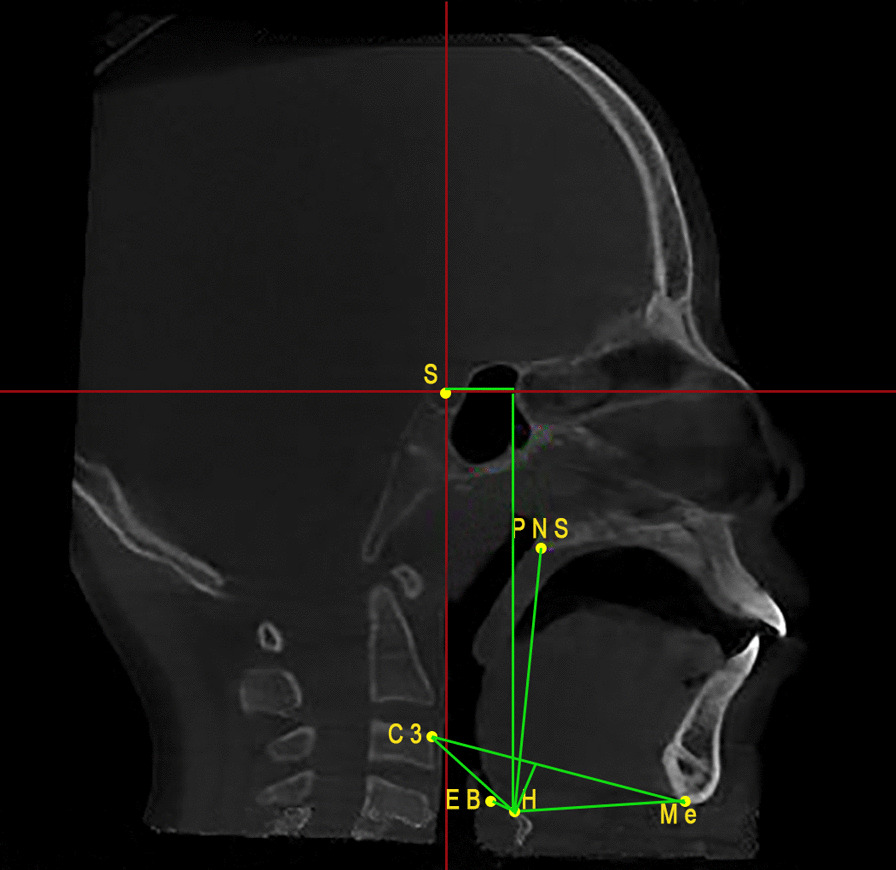

Hyoid bone measurements include eight linear measurements: H-Me, H-EB, C3-H, C3-Me, H-C3-Me, H-PNS, H–H, and H-V [14] (Table 1), (Fig. 3).

Fig. 3.

Hyoid bone landmarks and measurements